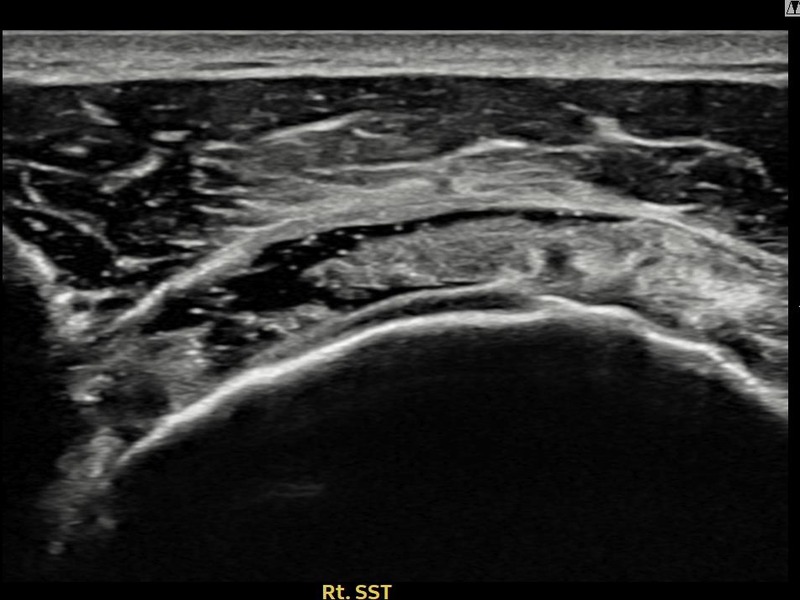

최ㅇㅇ님 · 우측 극상근건 관절면측 파열 진행형

우측 어깨 파열이 진행된 상태로 수술 없이 치료를 원해 내원하셨습니다. 다각도 초음파 평가 후 축소봉합술을 시행하여 힘줄 구조가 안정화되었습니다.

상세 보기 →